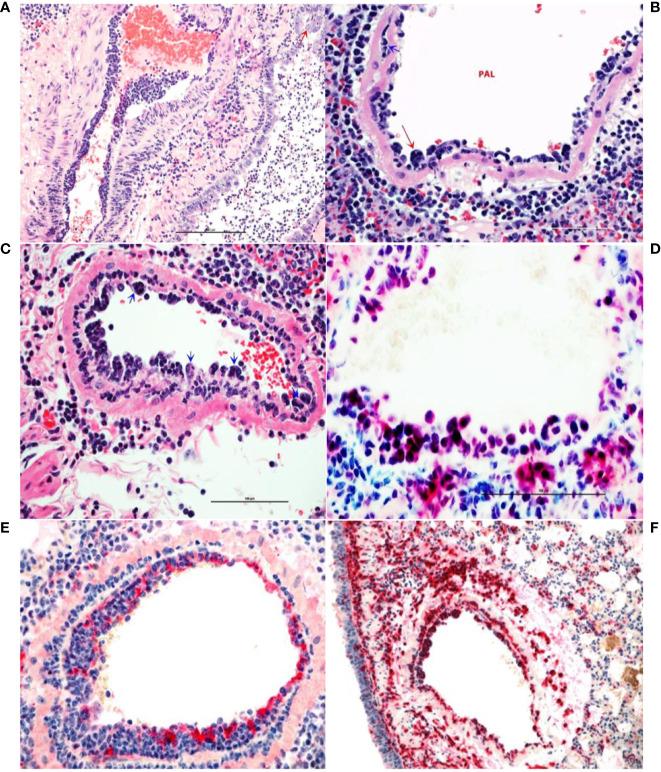

The emergence of COVID-19 has led to a pandemic that has caused millions of cases of disease, variable morbidity and hundreds of thousands of deaths. Currently, only remdesivir and dexamethasone have demonstrated limited efficacy, only slightly reducing disease burden, thus novel approaches for clinical management of COVID-19 are needed. We identified a panel of human monoclonal antibody clones from a yeast display library with specificity to the SARS-CoV-2 spike protein receptor binding domain that neutralized the virus . Administration of the lead antibody clone to Syrian hamsters challenged with SARS-CoV-2 significantly reduced viral load and histopathology score in the lungs. Moreover, the antibody interrupted monocyte infiltration into the lungs, which may have contributed to the reduction of disease severity by limiting immunopathological exacerbation. The use of this antibody could provide an important therapy for treatment of COVID-19 patients.